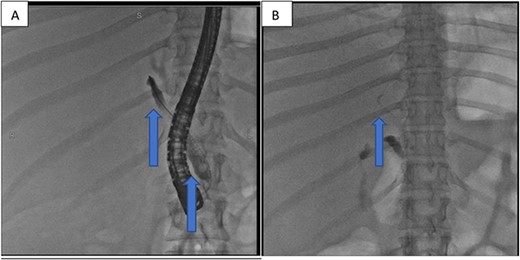

The following day, percutaneous drainage of the biloma was done through a pigtail catheter inserted through sub phrenic space access (Fig. 3). Subsequently after 6 days, drainage amount of the biloma markedly decreased and catheter was removed on the seventh day after insertion. The patient had marked symptom improvement afterwards, and control abdominal US was normal.

Insertion of percutaneous catheter drainage for drainage of biloma.